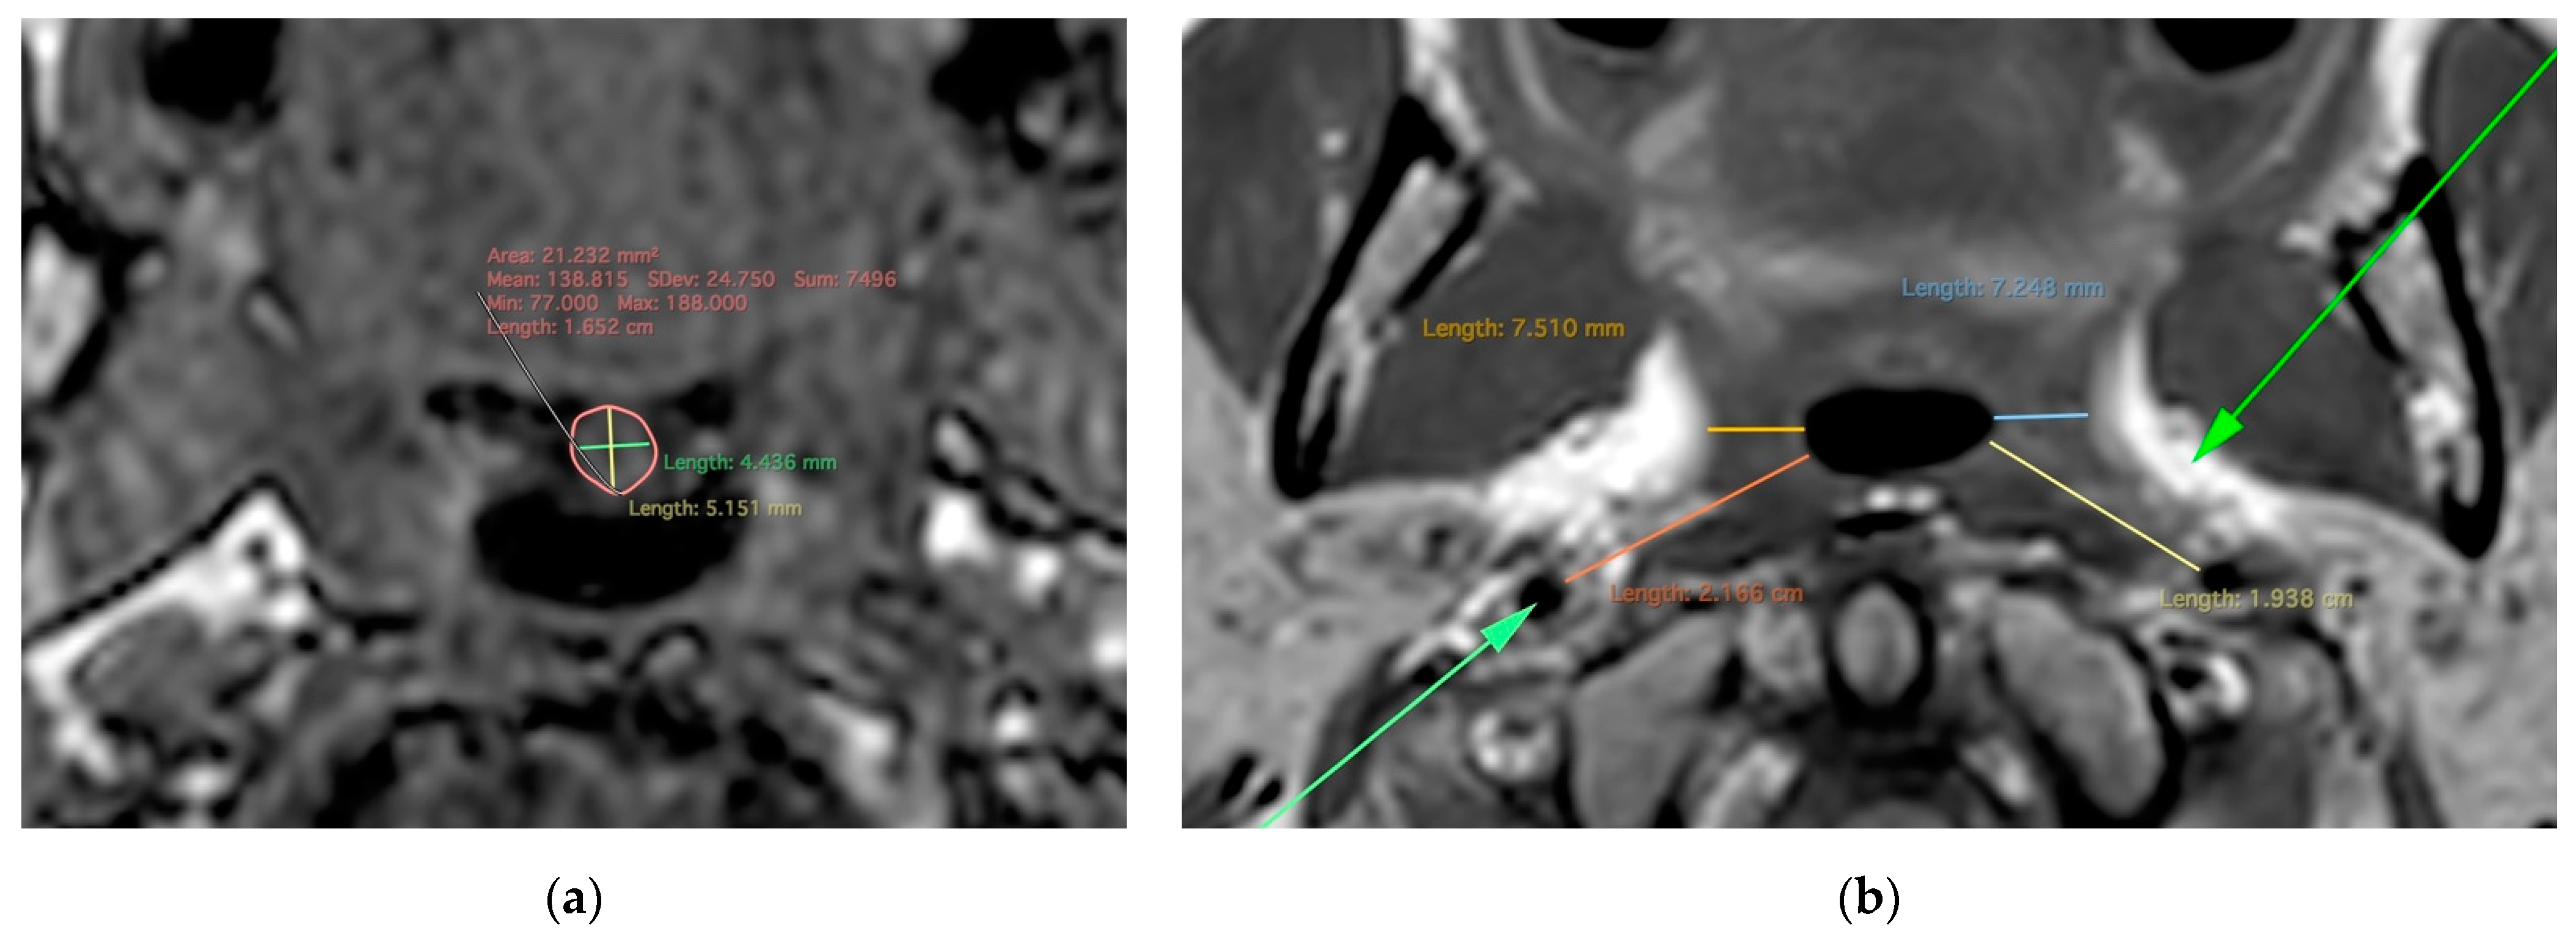

| Tongue anteroposterior diameter | A: 0.815 (0.633, 0.904) | C: 0 | E: 0.185 (0.096, 0.367) |

| Tongue thickness | A: 0 | C: 0.705 (0.490, 0.836) | E: 0.295 (0.164, 0.510) |

| Tongue axial width | A: 0 | C: 0.591 (0.334, 0.763) | E: 0.409 (0.237, 0.666) |

| Tongue volume | A: 0 | C: 0.625 (0.376, 0.786) | E: 0.375 (0.214, 0.624) |

| Tongue area | A: 0 | C: 0.532 (0.291, 0.698) | E: 0.468 (0.302, 0.709) |

| Subcutaneous neck fat thickness | A: 0.841 (0.719, 0.908) | C: 0 | E: 0.159 (0.092, 0.281) |